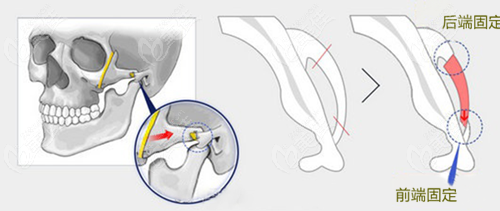

潘宝华颧骨内推如何?技术好、经历也丰富,潘宝华医生颧骨内推手术研发的“微创颧骨颧弓降低术”,承袭了日式自然协调的塑型风,手术主打的:微创、自然、不下垂。

①手术会从口内切开,尽有一个切口,大大降低留疤概率,避免出现手术痕迹明显等问题;

②同时,对颧骨两端截断,微创的方式做颧骨内推半折断固定,钛钉钛板固定,术后不容易有断层感;

③加上潘宝华颧骨内推还会做软组织提拉复位,降低术后下垂/松弛等问题,面部紧致,不容易显老。